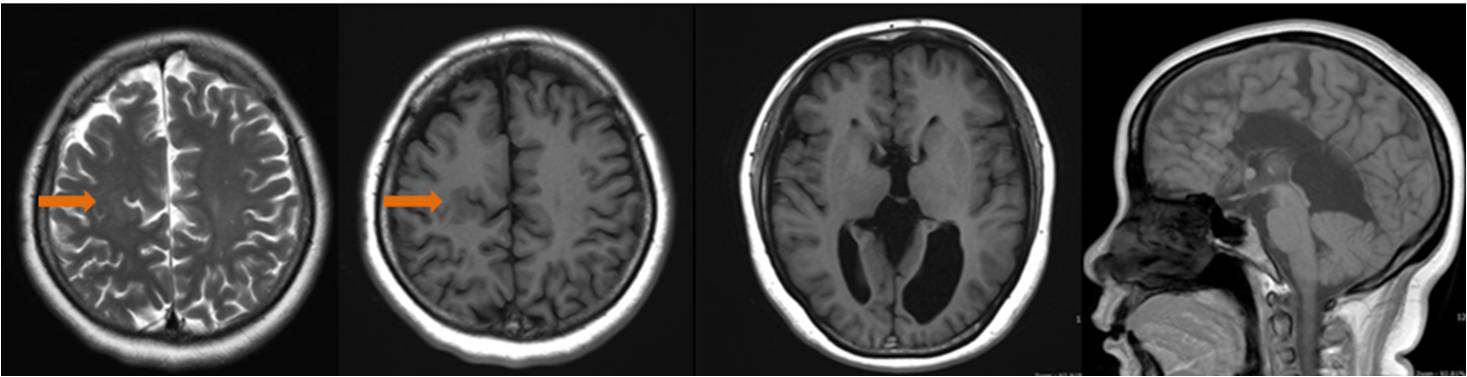

(一) 胼胝體發(fā)育不良合并腦灰質(zhì)異位、腦裂畸形

女,41歲,胼胝體缺如并腦裂畸形、灰質(zhì)異位(箭頭);雙側(cè)側(cè)腦室間距增寬,第三腦室擴大上抬插入側(cè)腦室之間,雙側(cè)側(cè)腦室前角變小,后角不規(guī)則擴大(左側(cè)為著),大腦大靜脈池囊狀擴大。